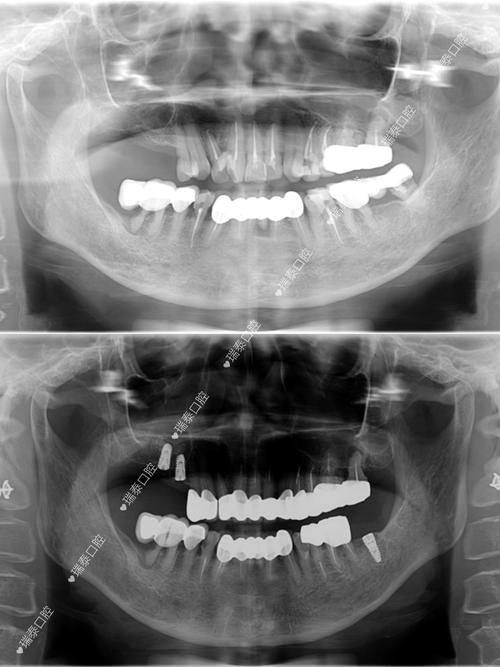

1. 种植牙:种植牙是西安弗莱堡口腔的特色与主打项目。医院设备齐全,拥有精良的数字化种植技术,能够借助完善的数字化设备精细测量患者口腔结构和骨骼情况,通过三维影像技术精细定位种植体位置,为种植方案设计提供详细的数据支持。同时,使用数字化导板确保种植体在手术中精细植入,减少手术时间,提高手术成功概率。此外,西安弗莱堡口腔还开展了all-on-4全口/半口即刻负重种植、穿颧穿翼疑难种植以及高龄种植技术等特色项目。其中,all-on-4全口/半口即刻负重种植可让患者在一次手术中完成多颗牙齿种植,大大节省治疗时间,还能提供更好的咀嚼功能和美观成效,提升患者生活质量。穿颧穿翼疑难种植则是针对牙槽骨萎缩、重度吸收等复杂疑难种植牙病例,西安弗莱堡口腔拥有经验多的医护团队和精良设备技术,能制定个性化治疗方案并取得良好成效。高龄种植技术方面,医院针对高龄患者有丰富的种植经验,医生团队会根据患者身体状况和口腔情况制定个性化治疗方案。

1. 蔡明河:口腔医院种植院长,高龄疑难种植学科医生,累计种植病例超数万名。擅长数字化口腔种植、即拔即种、即刻负重、高龄种植、半口/全口牙缺失复杂疑难种植技术等。

2. 赵森:口腔种植科副主医生,第四军大口腔医院毕业,有20多年临床种植经验,熟悉10多种韩系、欧美系进口种植牙操作系统,对各类牙齿缺失缺损修复经验多。擅长微创即刻种植、即刻负重即刻修复、全口半口种植、骨量不足植骨种植等。